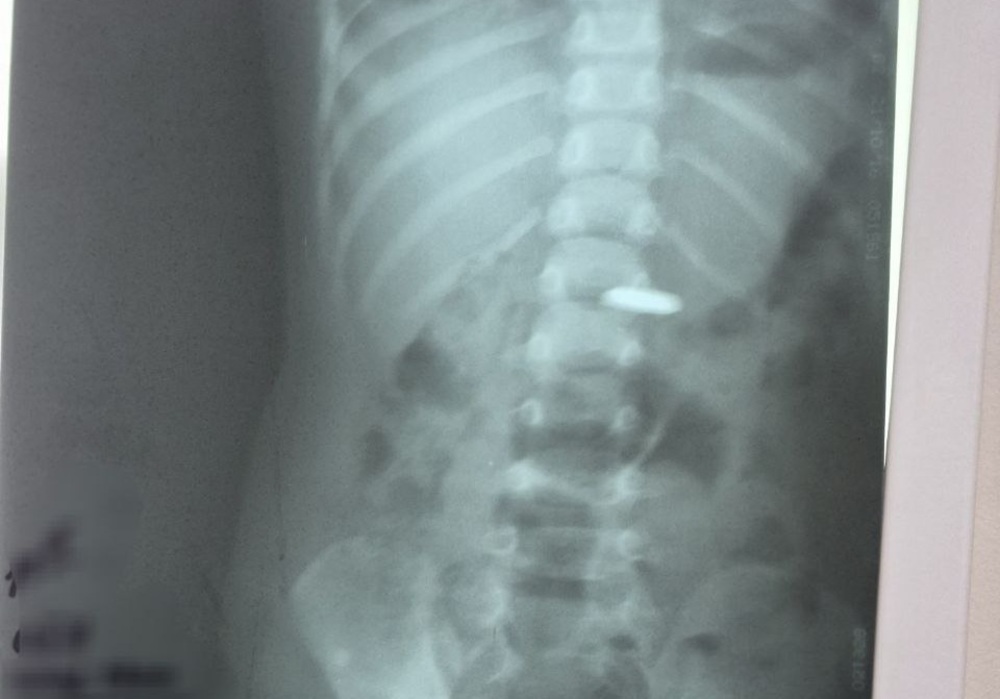

После поступления ребенка медики сделали рентген, который подтвердил наличие инородного предмета. Далее специалисты извлекли батарейку с помощью эндоскопа.